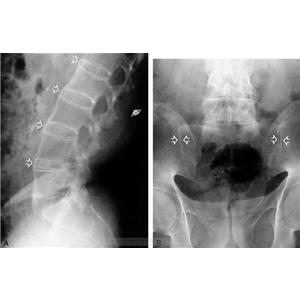

AS ①晚期 ②重度 病史:5年+

治疗后骶髂关节疼痛消失,腰椎前屈、背伸侧弯活动自如,膝关节无压痛感,复查血沉、C反应蛋白、等各项检查均已达到临床康复的标准。